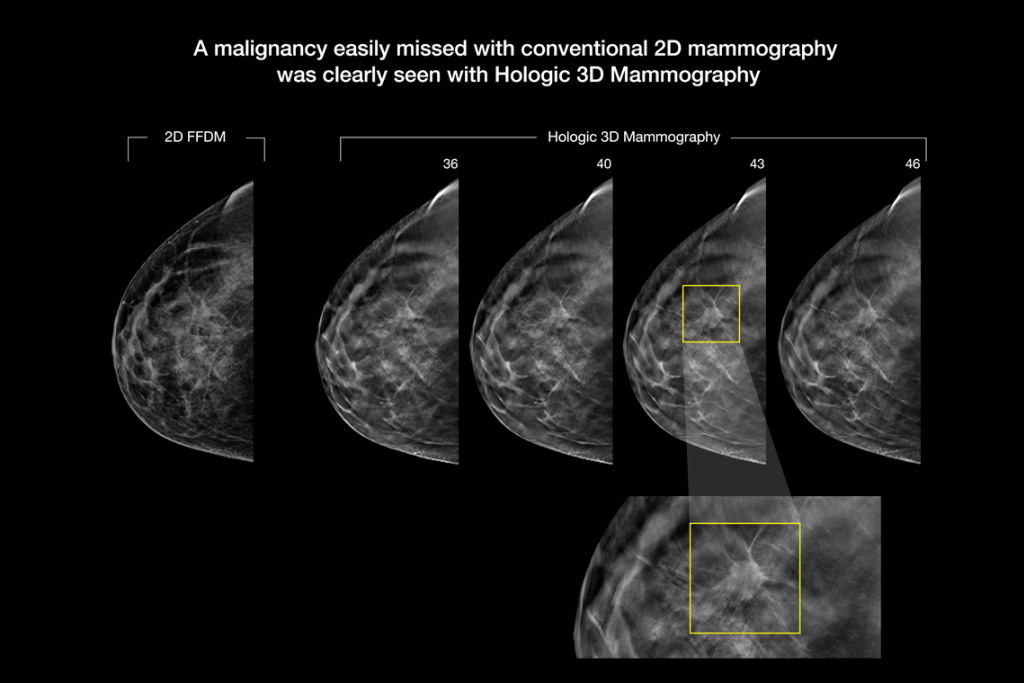

The Selenia Dimensions system delivers proven accuracy of our 3D Mammography exam to detect significantly more invasive breast cancers earlier and reduce call backs vs 2D alone.2-6,*

Detects up to 65% more invasive breast cancer, and reduces recalls by up to 40%, compared to 2D alone.2-4,*

Superior Accuracy

Superior accuracy for women with dense breasts compared to 2D alone.6

Clinical Images